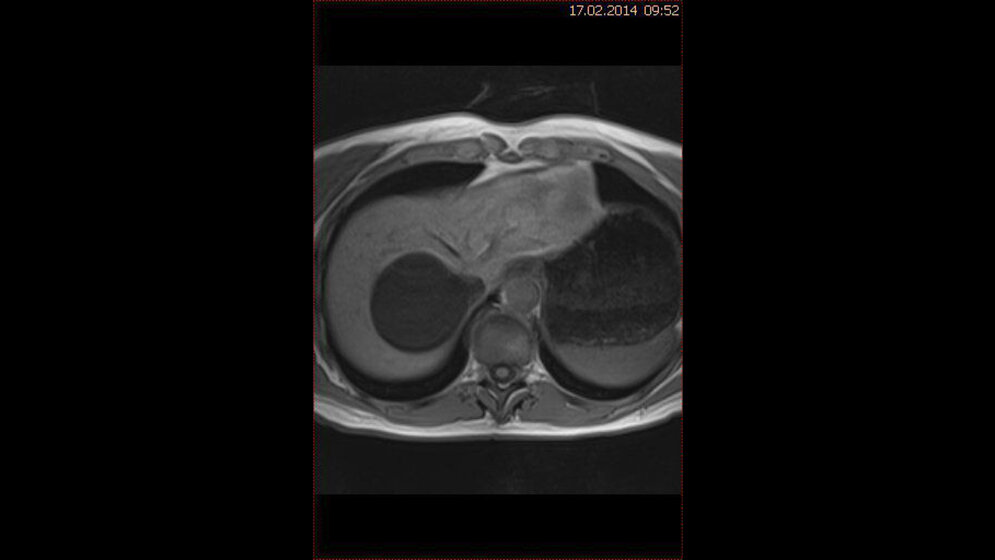

Zufallsbefunde: Leberzysten

In vorausgegangenen Beiträgen dieser Serie wurden schon zahlreiche Zufallsbefunde im Abdomen bei Schnittbilduntersuchungen der Lendenwirbelsäule beschrieben. Dabei hat insbesondere die MRT das Potenzial und Vorteile gegenüber der Computertomographie, angrenzende innere Organe zumindest teilweise zu erfassen.

Zystische Läsionen der Leber kommen in der klinischen Praxis relativ häufig vor. Sie können als twicklungsbedingte, neoplastische, infektiöse, entzündliche oder andere Läsionen klassifiziert werden. Im Ultraschall, der CT und MRT haben die Zysten spezifische Kennzeichen.